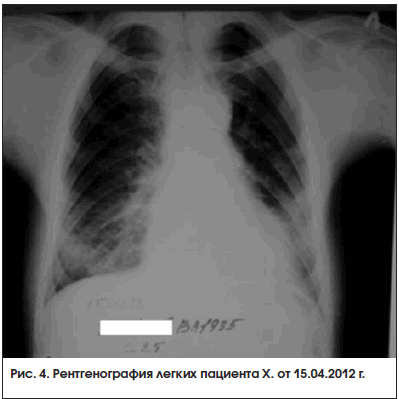

В период после назначения метотрексата и преднизолона до настоящего времени отмечается устойчивая положительная динамика состояния пациента. Он ведет активный образ жизни, исчезли кашель и одышка, нет ознобов и субфебрилитета, значительно уменьшились боли и отек в суставах, расширился объем движений. Несмотря на формирование контрактур в суставах кистей и лучезапястных суставах (рис. 2 и 3), обслуживает себя и выполняет работу по дому. При рентгенографии кистей в апреле 2012 г. суставные поверхности прослеживались, их контур четкий, кистообразной перестройки костной ткани нет. При рентгенографии легких от 15 апреля 2012 г. определялись двусторонний фиброз в нижних отделах легких с обеих сторон, формирование «сотового» легкого (рис. 4). В настоящее время получает метотрексат 10 мг/нед., преднизолон 10,125 мг/сут. Биохимические показатели снизились и составляют: КФК – 426 ммоль/л, КФК-МВ – 64 Ед/л, ЛДГ – 603 ммоль/л, СОЭ – 14 мм/ч.

Сохранение суставной симптоматики в виде дефигурации мелких суставов кистей, разгибательной контрактуры лучезапястных, пястно-фаланговых и проксимальных межфаланговых суставов, несмотря на минимальные рентгенографические изменения, требует дальнейшего наблюдения за пациентом на предмет выявления ассоциации ДМ с другим заболеванием соединительной ткани – в первую очередь с серонегативным ревматоидным артритом. Дисфагия и «синдром сотового легкого» также требуют дифференциальной диагностики с заболеваниями склеродермической группы.